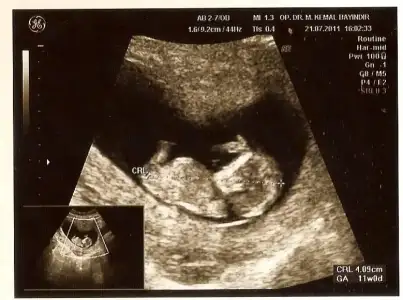

dr soylemeden siz gorun genital nub teorisi ( bebegin cinsiyeti)

Sanırım düzgün yükleyemedim ama anlaşılıyorsa benim görüntülere de bakın 12. Haftada çekildi:)

canim duz yukleyemezmisin ama bebegin sanki erkekk :)) duz gorebilseydim yanilayorda olabilerem

himmmm bak burda paralel gibi duruyor nubu

buarada dr un ismi dikkatimi cekti dr bayindir erkek bebek icin bayaa bi yardimci oluyormus yakin olsaydim kesin giderdimm :))

kac haftalik canim burda sanki 11 gibi bu haftalar cok yaniltici oluyor baska fotosu varsa koyarmisin